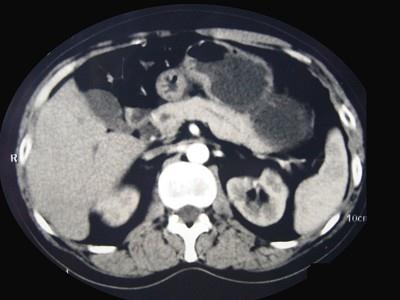

问题 男性,57岁,1年前无明显诱因反复出现嗜睡及发作性神志不清,进食糖水或甜品后症状即缓解,腹部CT检查如下图,最佳的诊断是 ( )

选项 A、胃泌素瘤 B、舒血管活性肽瘤 C、胰岛细胞瘤 D、胰腺转移瘤 E、胰腺癌

答案 C